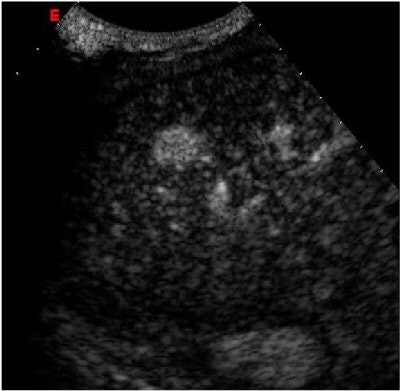

![]() |

| Above: Ultrasound study of an early-stage hepatocellular carcinoma. At baseline examination, the lesion is iso-hypoechoic and hardly detectable. Below: After injection of the contrast agent SonoVue (Bracco), the tiny nodule clearly stands out against the surrounding liver parenchyma due to its arterial vascular supply. Images courtesy of Bracco and Dr. Riccardo Lencioni, University of Pisa, Italy. |